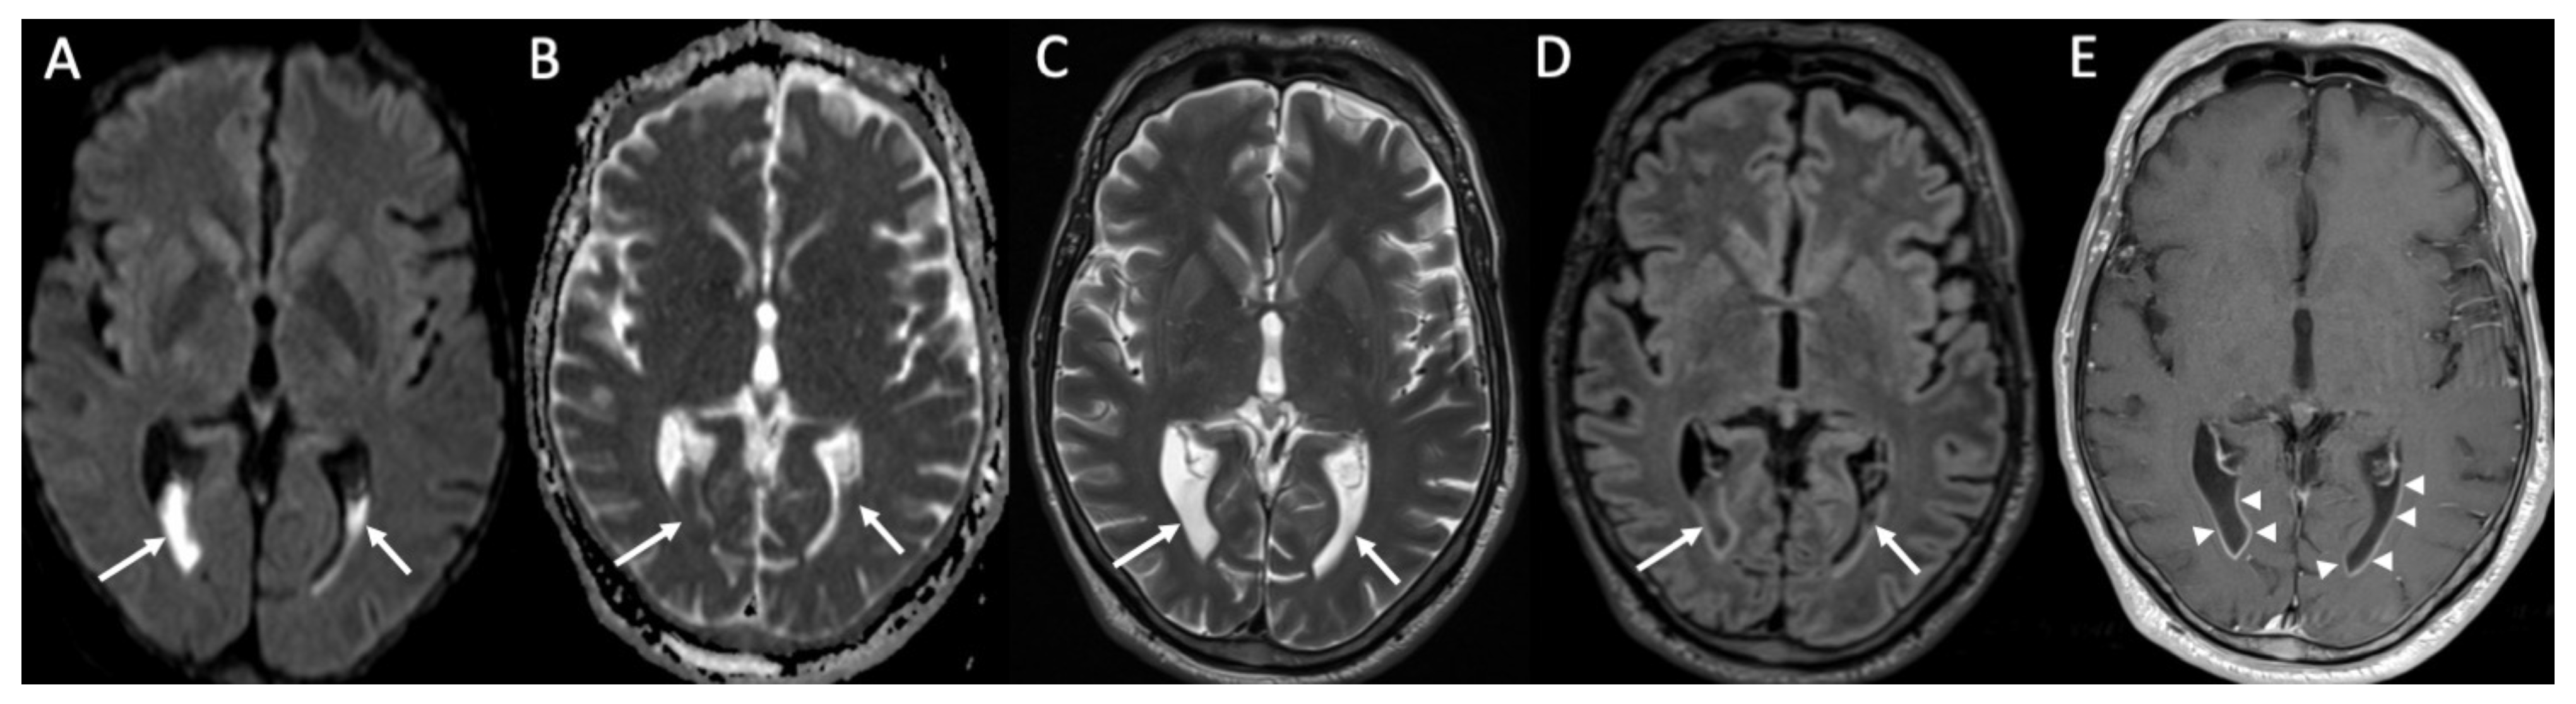

| Tuberculosis | • Leptomeningeal enhancement in the basal cisterns • Hydrocephalus very common • Infarcts in the basal ganglia due to vasculitis • Possible concomitant tuberculomas or miliary tuberculosis |

- Patkar, D.; Narang, J.; Yanamandala, R.; Lawande, M.; Shah, G.V. Central Nervous System Tuberculosis. Neuroimaging Clin. N. Am. 2012, 22, 677–705. [Google Scholar] [CrossRef] [PubMed]